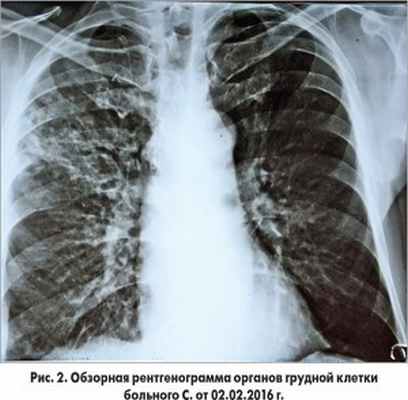

27.01.2016 г. проведено стентирование инфарктобусловившей коронарной артерии стентом без лекарственного покрытия. В этот же день на рентгенограмме органов грудной клетки, выполненной в вынужденном горизонтальном положении в условиях палаты, были выявлены изменения, вызывающие подозрение на негоспитальную (2-е сутки пребывания в стационаре) правостороннюю пневмонию (рис. 1).

Пациент продолжал получать ацетилсалициловую кислоту, клопидогрель, аторвастатин, эналаприл, бисопролол, пантопразол, эплеренон. На рентгенограмме от 4.04.2016 г. (70-е сутки наблюдения) отмечалась выраженная положительная динамика в виде рассасывания инфильтративных изменений в легких и исчезновения плеврального выпота (рис. 6).